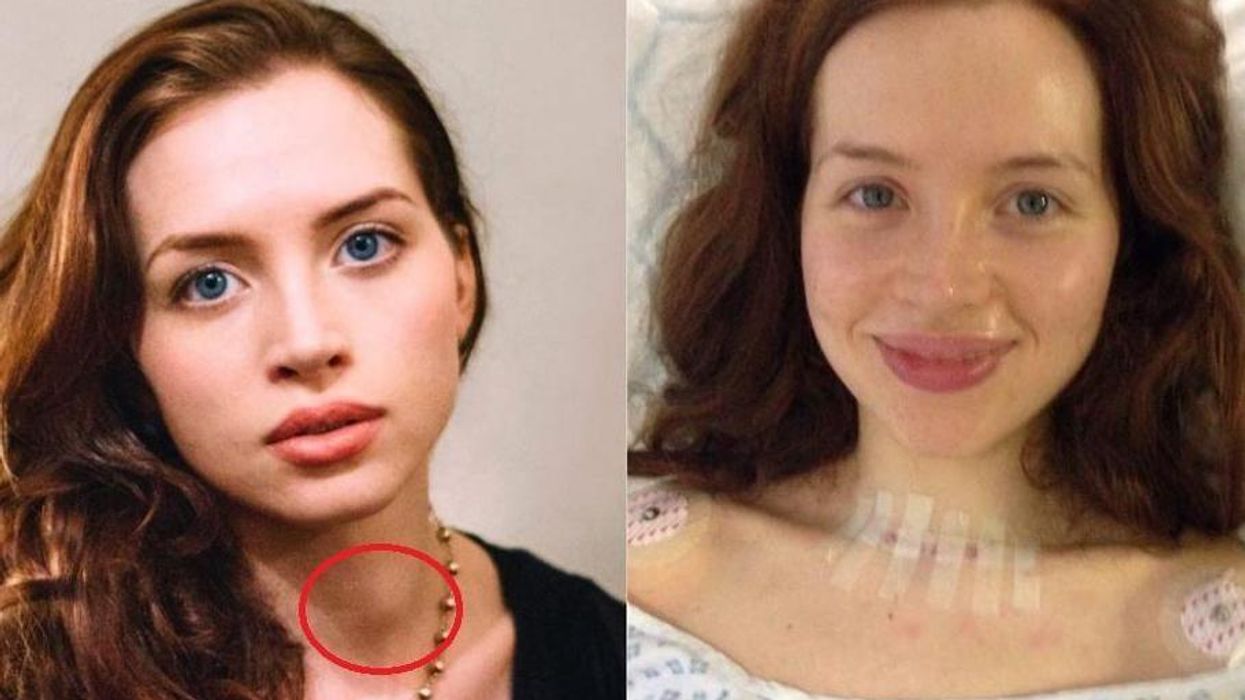

This Photograph Shows A Little Known Symptom Of Thyroid Cancer

Thyroid Cancer Symptoms And Signs Dana Farber Cancer Institute